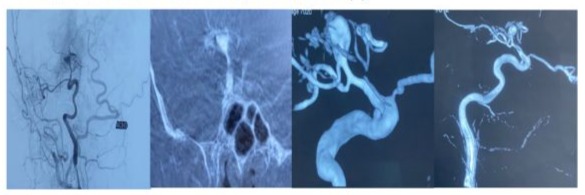

H.E a 26-year-old man with a history of active smoking, cannabis use, and chronic alcohol consumption. He had no history of recurrent tonsillitis, childhood heart disease, autoimmune disorders, known hereditary diseases, cervical trauma, or heavy lifting. He was admitted to the neurological emergency unit 3 days after sudden onset of proportional left hemiplegia, dysarthria, and Claude Bernard-Horner syndrome. An urgent brain CT scan revealed an ischemic stroke in the middle cerebral artery territory with a hyperdense sylvian artery sign (Figure 1). Brain MRI showed an intracranial dissection of the right carotid and sylvian arteries (Figure 2). One week later, digital subtraction angiography revealed a pseudoaneurysmal dilation at the origin of the right sylvian artery, resulting from the progression of the intracranial dissection (Figure 3). The patient was placed on antiplatelet therapy. The etiological assessment of his ischemic stroke revealed mitro-aortic infective endocarditis complicated by an abscess of the membranous septum, severe aortic regurgitation, and moderate mitral regurgitation. Notably, his initial Transthoracic Echocardiography (TTE) six days prior revealed infected endocarditis without concomitant valvulopathy. Blood cultures were negative. Biological analyses showed absence of inflammatory syndrome with negative Procalcitonin, positive TPHA and VDRL serology in the blood, while Cerebrospinal Fluid (CSF) analysis revealed a clear, normotensive fluid with normal biochemical and bacteriological findings and negative TPHA and VDRL serology in the Cerebrospinal Fluid (CSF), the other serologies (serology of hepatitis B and C, HIV) were negative. The patient received intravenous antibiotic therapy with ceftriaxone (2g/day) for six weeks and gentamicin (160mg/day) for two weeks, with an indication for valve replacement surgery. Neurological deficits partially regressed (NIHSS at first day=9, at one month=5, and at three months=2, with a modified Rankin Scale score of 3 at three months).

Figure 3: Three-dimensional angiography demonstrating pseudoaneurysmal dilation at the origin of the right sylvian artery with small caliber appearance of the internal carotid artery with spasms indicating the presence of vascular pathology in a drug user.